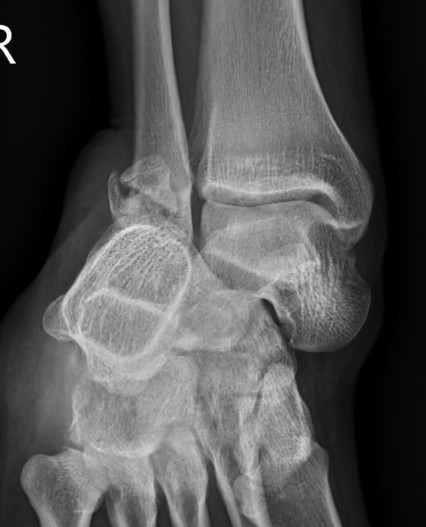

Lateral subtalar dislocation with fracture of the lateral malleolus

2. Lateral

- calcaneum dislocated laterally

- high energy trauma

- often associated with fractures

- can be difficult to reduce due to incarceration of tibialis posterior and FDL